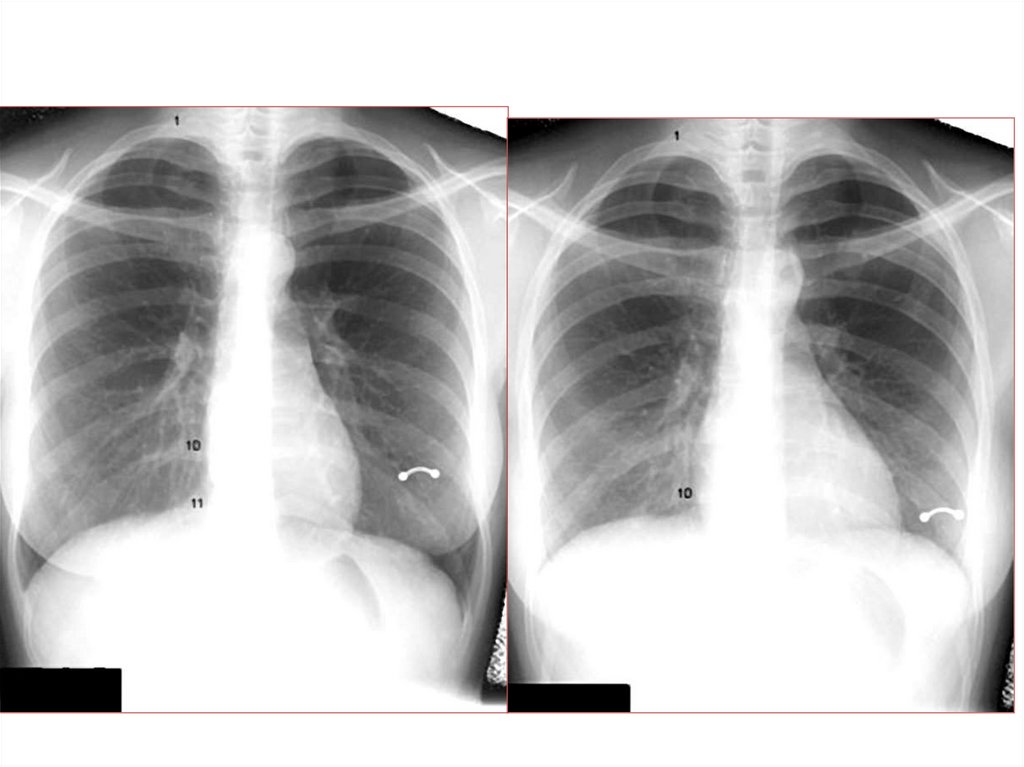

Рентгенография

5.